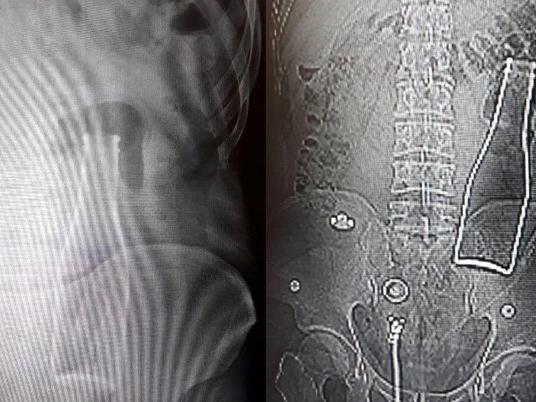

Bunun üzerine röntgen filmi çekilen gencin kalın bağırsağında şişe olduğu görüldü. Makattan girdiği belirlenen şişe, yaklaşık bir saat süren ameliyatla çıkarıldı.